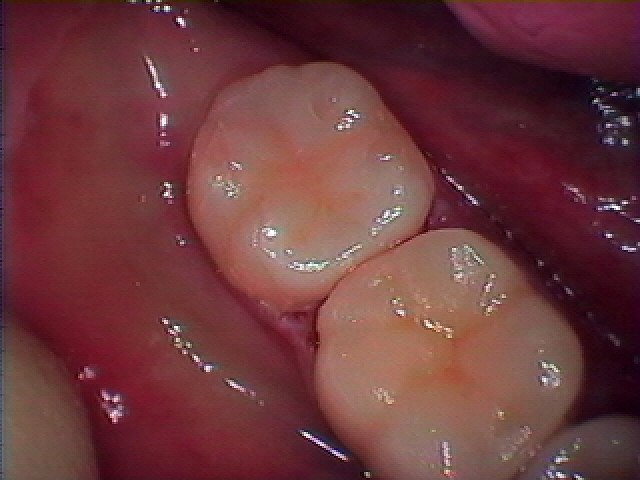

奥の7番も外して中の虫歯の存在がありました

CR樹脂にて覆罩して型取りを行い、きれいなセレックセラミックを

入れていきました

きれいに仕上がりました

インプラント部も良好です